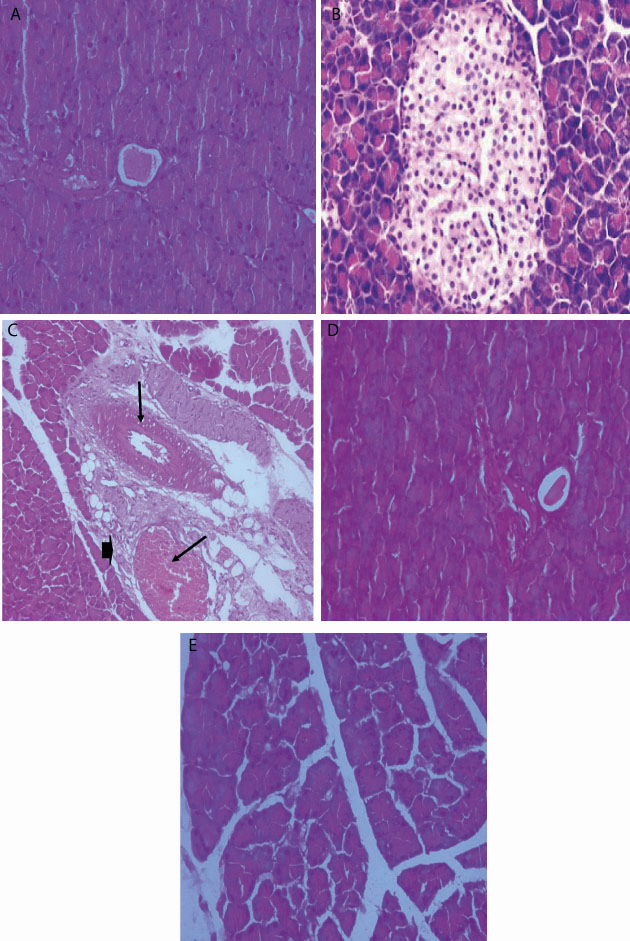

Fig. 2: Histopathological examination of pancreas tissue. A (negative control) and B (DMSO) showed apparently healthy parenchyma, note the normal pancreatic acini and islets, C (Positive control) showed congestion of the blood vessel with thickened wall (arrow) together with fibrous connective tissue proliferations (arrow head), D (Metformin) showed apparently healthy parenchyma, note the normal pancreatic acini and islets, E (Rutin) showedapparently healthy parenchyma, note the normal pancreatic acini and islets

The normal pancrease section of control and DMSO group showed healthy n parenchyma, normal pancreatic acini and islets. In positive group showed congestion of the blood vessels with thickened wall with fibrous connective tissue proliferation. Treapeutic and standard group showed healthy parenchyma, normal acini and islets (fig. 2).